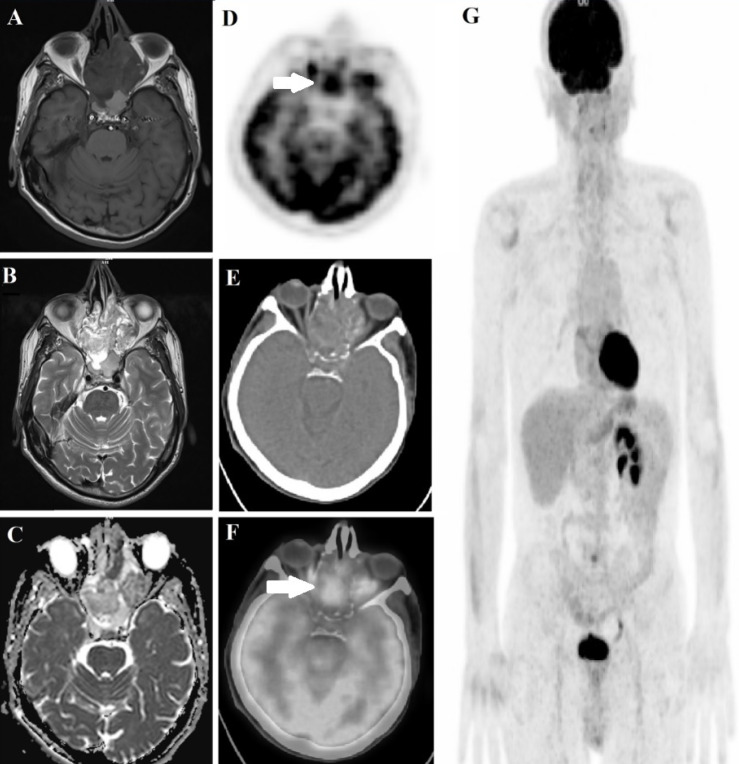

A rare tumor, intestinal-type adenocarcinoma (ITAC), accounts for 8-25% of all sinonasal malignancies. The tumor's histological resemblance to gastrointestinal tract adenocarcinoma is implied by its name. ITAC develops in the ethmoid sinus and upper nasal cavity. Herein, we present sinonasal ITAC with increased prostate-specific membrane antigen expression and fluorodeoxyglucose uptake.